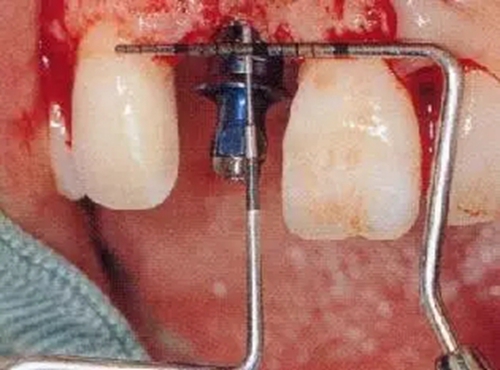

▲圖44-7,8

7個(gè)月后,牙齦組織的愈合狀態(tài)。

圖44-9~11 種植體植入時(shí)的狀態(tài)。將種植體邊緣植入低于兩鄰牙的牙齦線連線3mm的位置。頰舌方向則位于距唇側(cè)CEJ1mm的位置。